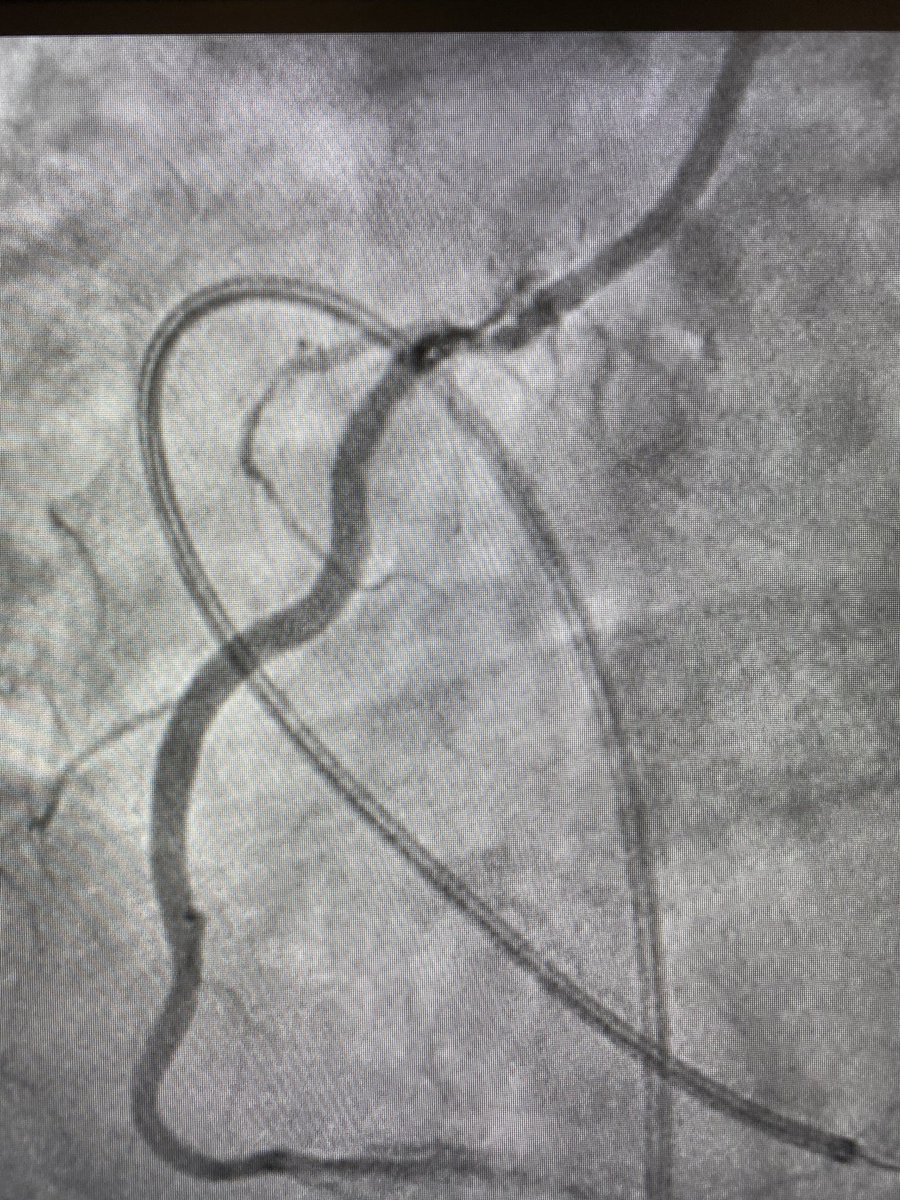

After considering making an early transition to industry but struggling to walk away from the lab, damn it feels good to get the #CHIP train rolling again! 1st #PercAx LM #rotapro in NJ & single #safefemoral access with 7fr dest via CP. Off-label but 💯! Props to @jason_wollmuth

RajTayalMD's tweet image. After considering making an early transition to industry but struggling to walk away from the lab, damn it feels good to get the #CHIP train rolling again! 1st #PercAx LM #rotapro in NJ & single #safefemoral access with 7fr dest via CP. Off-label but 💯! Props to @jason_wollmuth